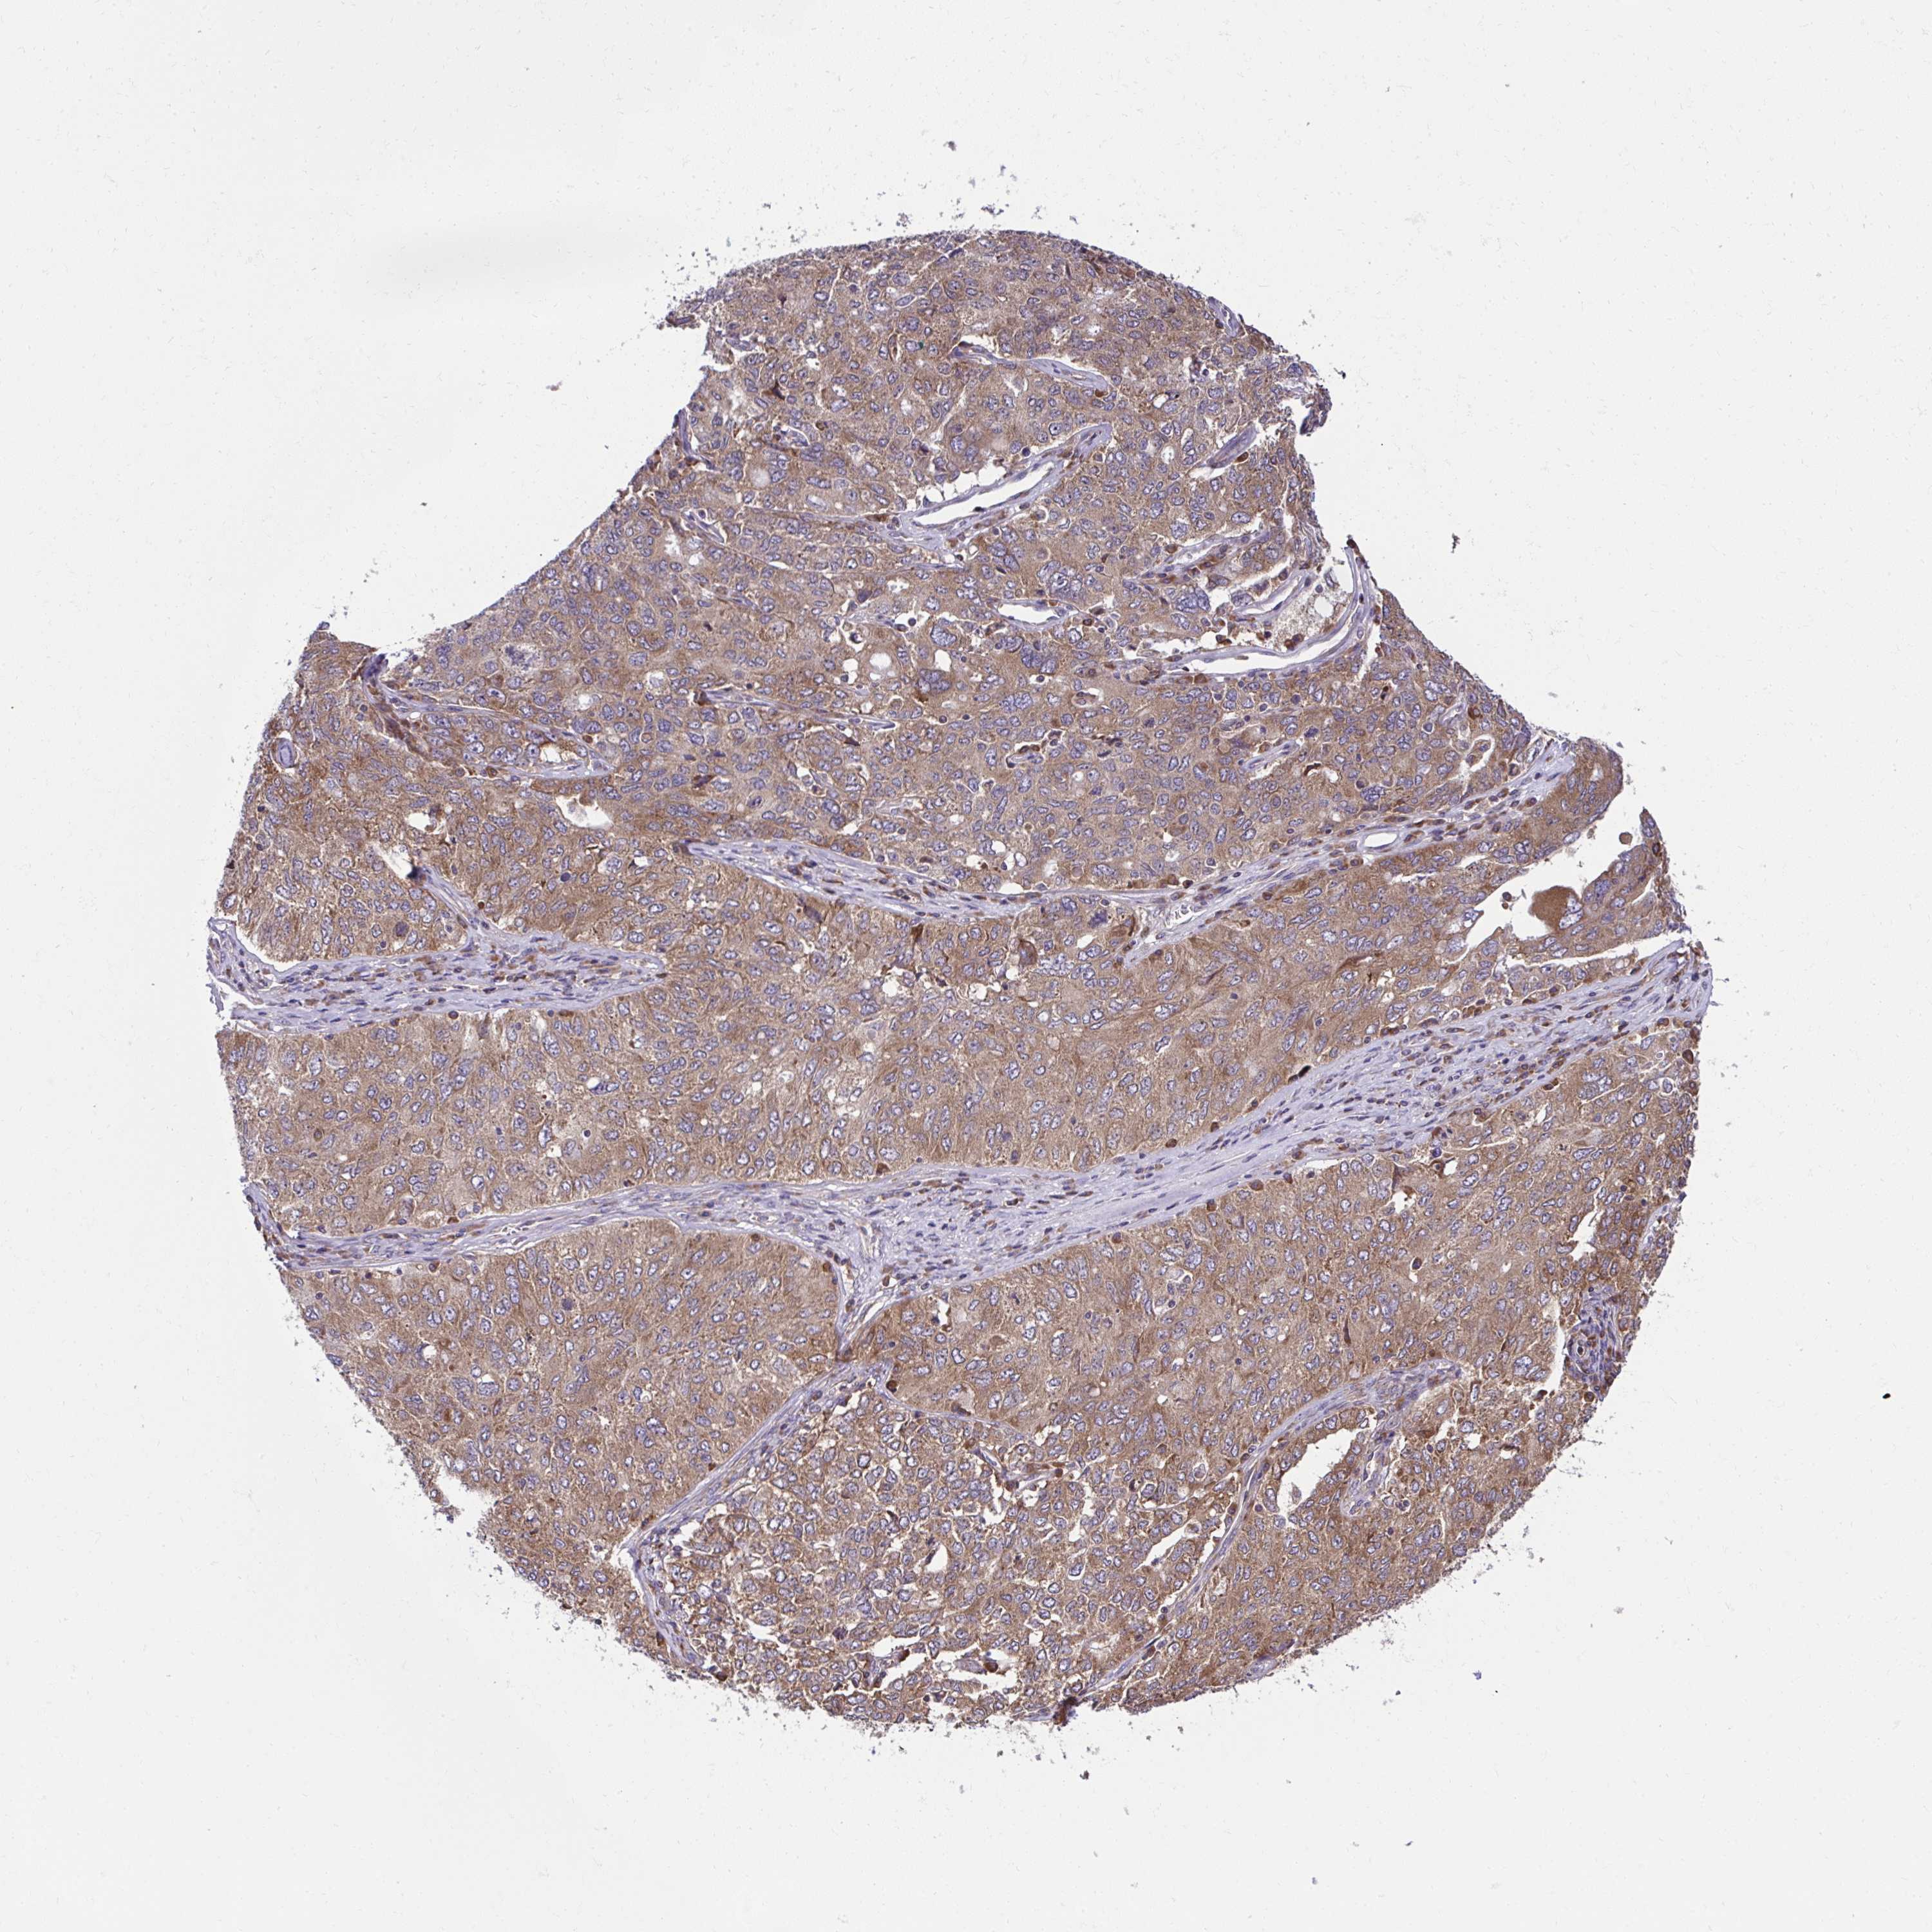

OVARIAN CANCER - Protein expressioni

A mouse-over function shows sample information and annotation data. Click on an image to view it in a full screen mode. Samples can be filtered based on level of antibody staining by selecting one or several of the following categories: high, medium, low and not detected. The assay and annotation is described here.

Note that samples used for immunohistochemistry by the Human Protein Atlas do not correspond to samples in the TCGA dataset.

Antibody stainingi

Antibody staining in the annotated cell types in the current human tissue is reported as not detected, low, medium, or high, based on conventional immunohistochemistry profiling in selected tissues. This score is based on the combination of the staining intensity and fraction of stained cells.

Each image is clickable and will lead to virtual microscopy that enables deeper exploration of all samples and also displays staining intensity scores, fraction scores and subcellular localization as well as patient and tissue information for each sample.

Antibody HPA056586

Staining

High

Medium

Low

Not detected

Intensity

Strong

Moderate

Weak

Negative

Quantity

>75%

75%-25%

<25%

None

Location

Nuclear

Cytoplasmic/membranous

Cytoplasmic/membranous,nuclear

Cystadenocarcinoma, serous, NOS

Carcinoma, endometroid

Cystadenocarcinoma, mucinous, NOS

Carcinoma, NOS